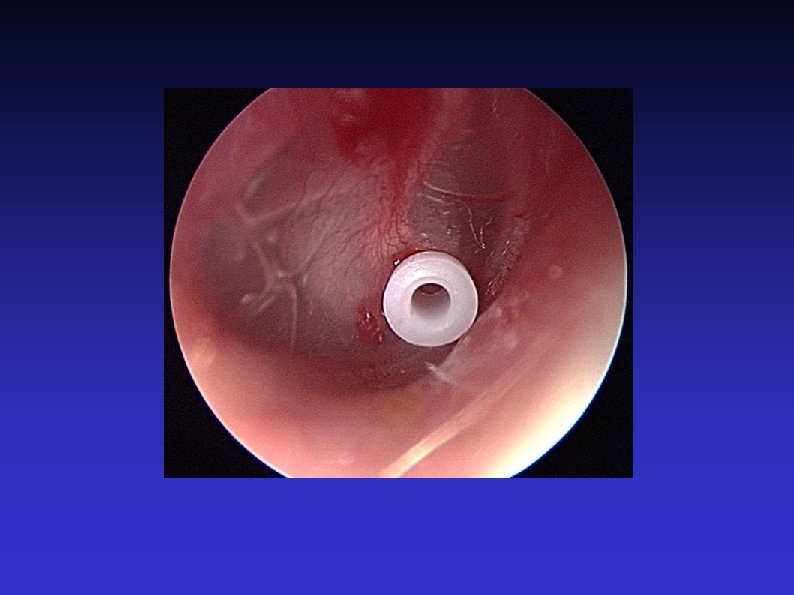

Examination of the Ear 7) Otoscopic examination The lateral process and handle of the malleus lie towards the centre of the tympanic membrane Four quadrants Perforation Central or marginal What can be seen through it Mastoid cavity Dry Wet, inflamed